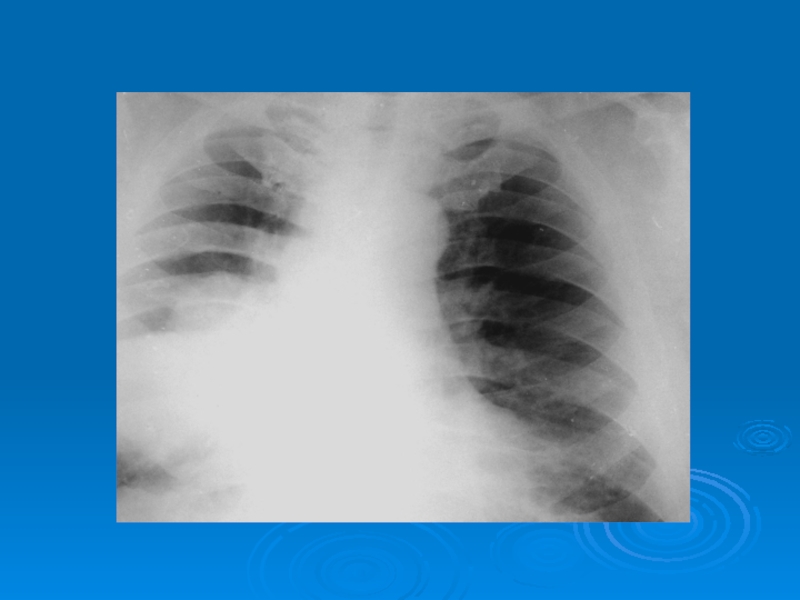

Слайд 44Рентгенограммы больных с абсцессами в правом и левом легком

Рентгенограммы больных с абсцессами в правом и левом легком